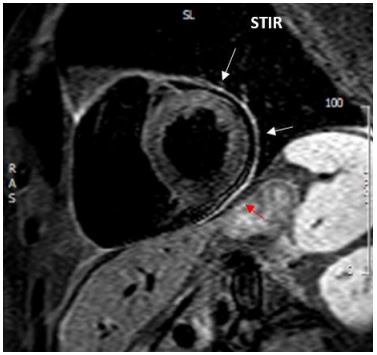

Figure 4:Cardiac magnetic resonance showing diffuse increased signal of the pericardium on T2 STIR image corresponding to inflammation of the pericardium.

Cardiac magnetic resonance finally confirmed the diagnosis of acute pericarditis, by demonstrating diffuse inflammation and oedema of the pericardium (Figure 4). Pericardial late gadolinium enhancement (LGE) was also detected (Figure 5).